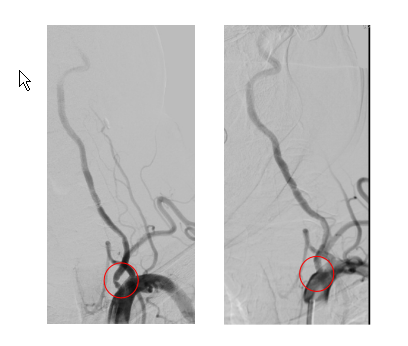

近日,一位68岁的老年男性患者,因“脑梗死后三年,出现头晕,行走不稳”就诊于我院神经内科,行颅脑CTA提示多发颅内大血管狭窄,为进一步诊治收入院。同时该患者有高血压病史20余年,冠心病,劳力型心绞痛病史近10年,虽然平素服用单硝酸异山梨酯、地尔硫卓等药物,但冠心病控制不佳,心绞痛仍时有发作。患者入院后,神经内科张小峰主治医师为该患者完善了全脑动脉造影,提示患者左侧椎动脉开口重度狭窄,这正是引起患者头晕症状的主要原因,但张医师并没有盲目为患者实施介入治疗,而是结合患者病史以及入院后的辅助检查结果,认为该患者可能同时存在脑血管,冠状动脉等多部位粥样硬化斑块及血管狭窄,为了减少患者痛苦,经与心脏内科薛亚军医师会诊共同商讨后,决定由两科介入团队联合完成冠状动脉和脑血管造影检查,一次性完成心脑血管评估,并同步开展脑血管介入诊疗及冠心病介入诊疗。经过充分准备后,2019年6月20日,神经内科张小峰医师带领王也医师及其介入团队通过股动脉途径,首先为患者顺利完成左侧椎动脉起始部位狭窄病变的介入治疗,植入一枚支架,保证了脑灌注(如图1)。随后心脏内科介入团队,在王伟民教授带领下,薛亚军与缪国斌医生通过神经内科已经建立的股动脉通路,为患者顺利完成冠状动脉造影,结果提示患者冠状动脉病变极其严重,医学上称为“左主干+三支冠脉病变”,如果不及时处理,随时有生命风险,王伟民教授果断为患者实施了左主干、前降支及回旋支分叉病变的介入治疗,并植入支架,顺利开通了闭塞的血管(如图2),挽救这位患者岌岌可危的心脏,整个介入手术过程耗时不足2小时,患者清醒,无任何痛苦,术后仅在腹股沟处留有一个约米粒大小的穿刺点,术后6小时就能够坐起并下地活动,真正体现了微创、快速、安全及准确的救治理念。5天后,心脏内科又经桡动脉为其完成右冠脉的介入治疗,彻底解决患者多年来的“心”病,经过两科室的联合精心救治,患者于2019年6月28日康复出院。出院时患者对我院的整个治疗过称给予了高度的评价,并表示了真挚的感谢(图3)。

图1 神经内科对患者左椎动脉介入治疗前后对比(左图术前,右图术后)